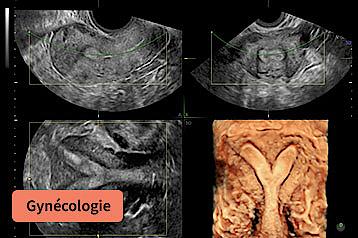

L’échographie de l’utérus hostile, l’endométriose et l’infertilité

• Introduction : Les outils à ma disposition pour l’échographie gynécologique sur mon Voluson

• Endométriose et diagnostic différentiels

• Bilan d’infertilité : le Fertiliscan et apport de l’HyFoSy

• Utérus hostiles : Adénomyose, Malformations Utérines, Polypes & Myomes, Synéchies & Isthmocèles